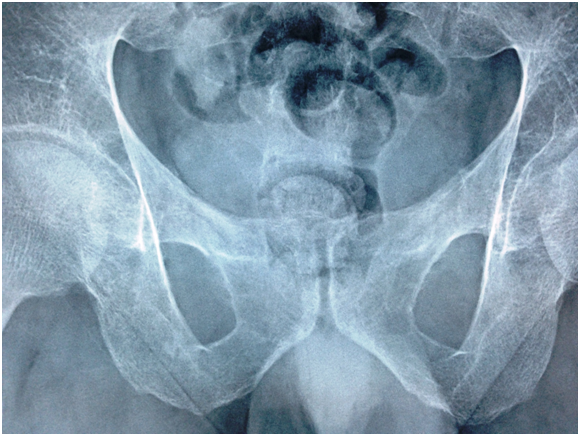

Pelvis –x-ray nov.22.2009

- R The Bones shows severe osteopenia, with appearance of Looser’s zones in the superior pubic rami, consistent with Osteomalacia…

Skeletal X-Ray: 6 months later

- Pelvis & both Femori: there is thickening of secondary bone trabeculae ,in the neck and metaphysis of both femori indicating osteopenia

- Upper Limbs & legs: normal cortical thickness but there is also thickening of secondary bone trabeculae in the distal tibia and fibula

- No Looser’s zones were detected.